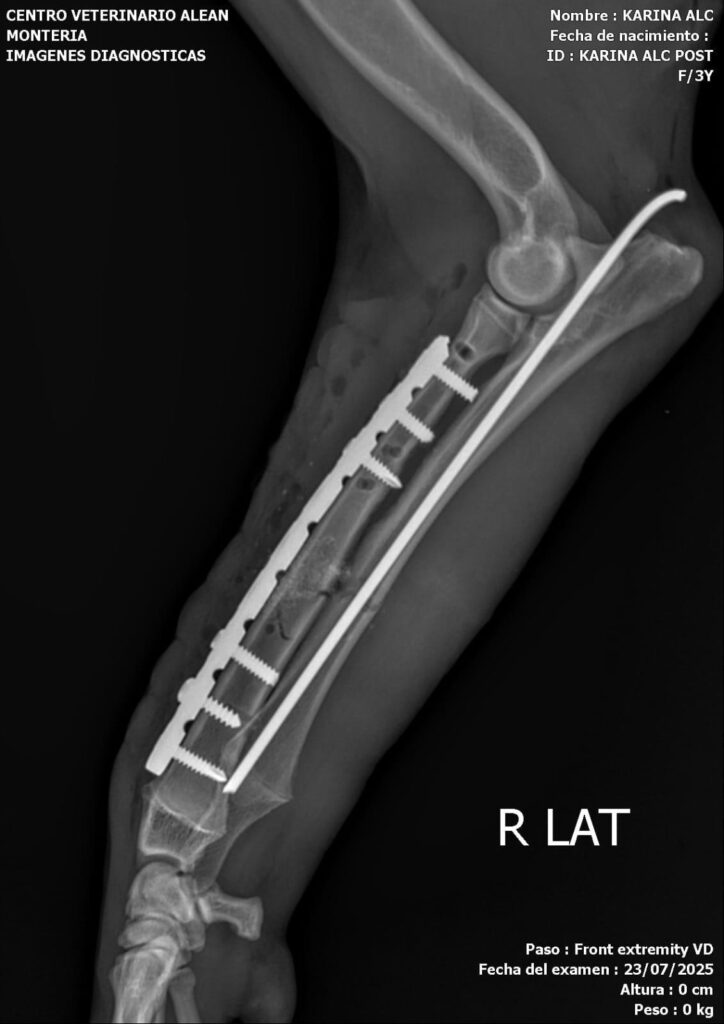

Hoy fue sometida a una tercera cirugía en la mandíbula, en la que se realizó una reconstrucción completa y una reducción total del radio. Además, se le colocó un sustituto óseo a base de silicofosfatos de sodio-calcio en el radio y la ulna.